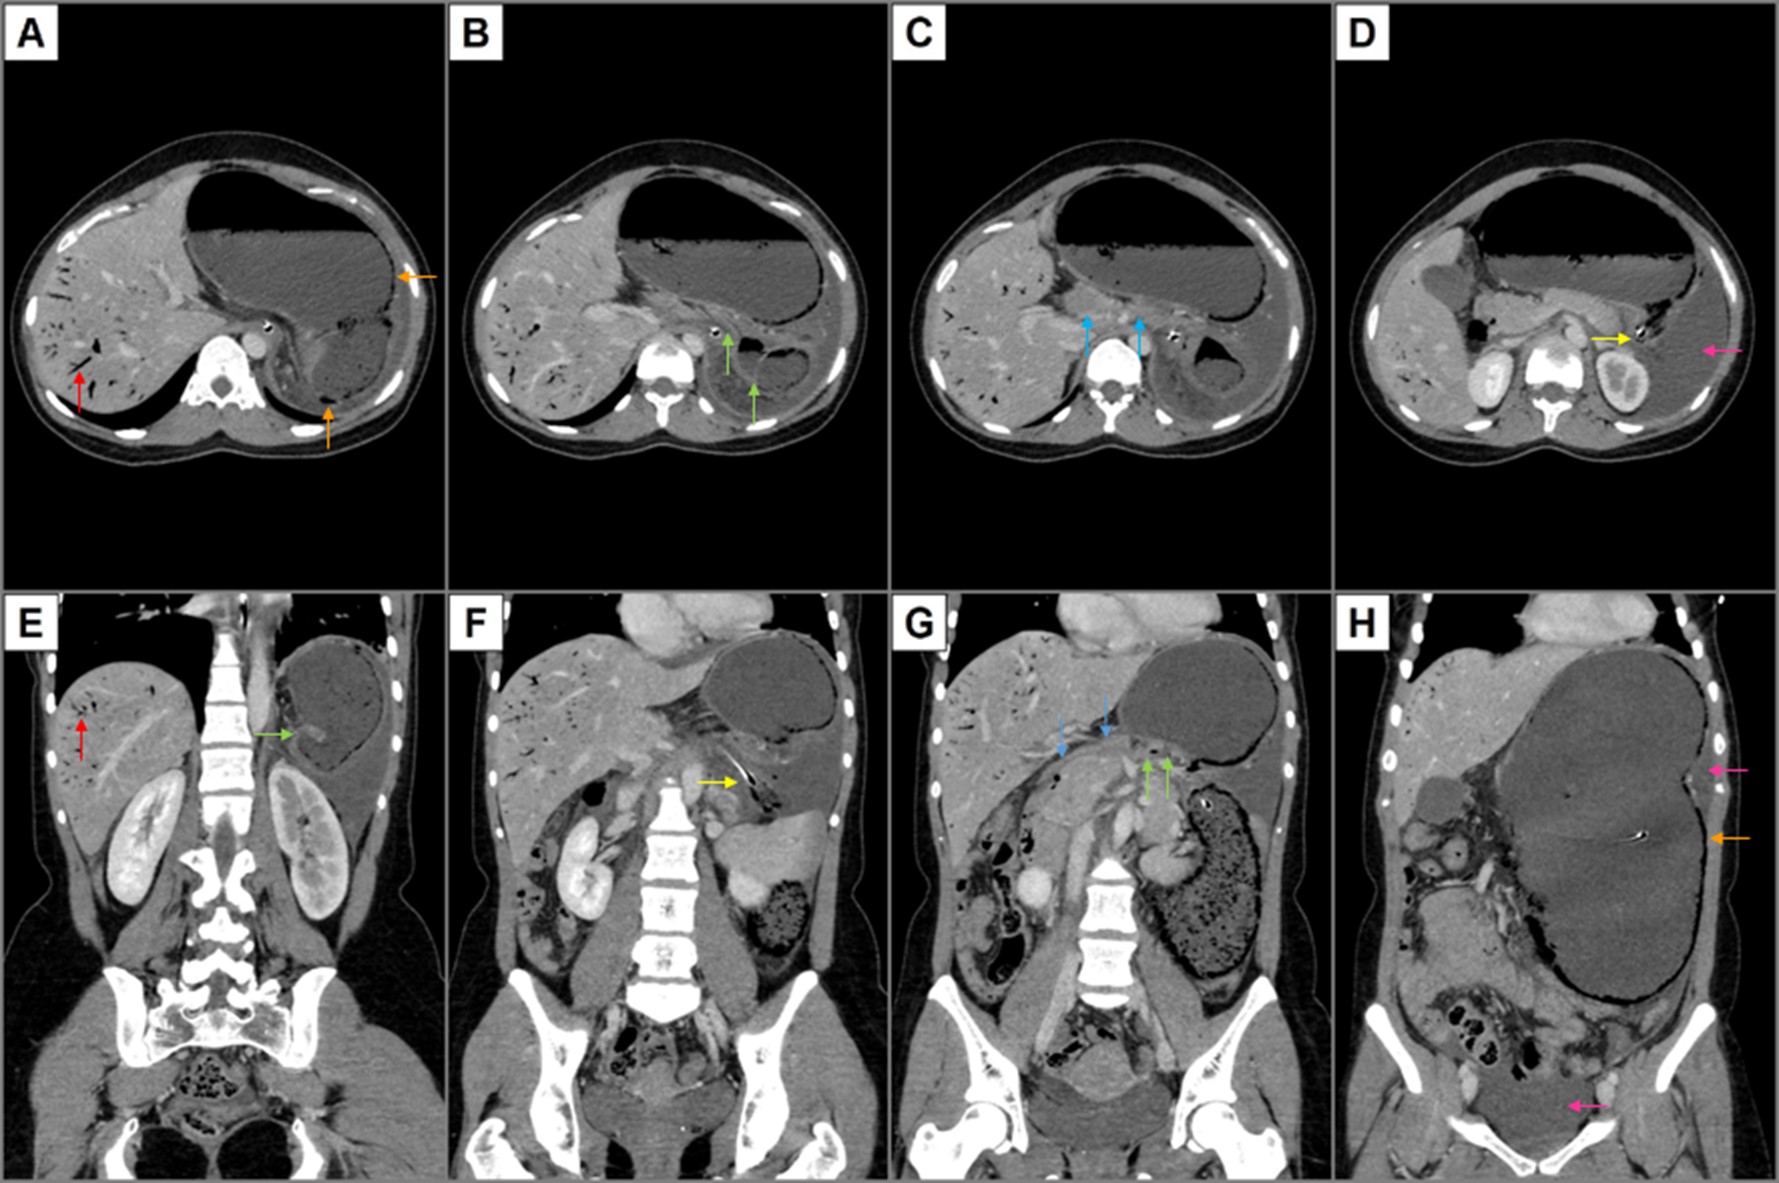

Neste contexto, foi requisitada TC abdominal e pélvica, que revelou como achados mais relevantes marcada distensão e alteração da posição do estômago com inversão da relação espacial entre a junção esófago-gástrica e o antro/piloro - junção esófago-gástrica localizada mais caudalmente e antro/piloro localizados mais cranialmente -, assim como pneumatose parietal gástrica e aeroportia (Figura 1). O conjunto destes achados fez sugerir o diagnóstico de vólvulo gástrico mesentero-axial complicado com isquemia gástrica.

Figura 1: TC abdominal e pélvica - Cortes axiais - de superior para inferior (A-D) - e coronais - de posterior para anterior (E-H) - de TC abdominal e pélvica revelando significativa distensão e alteração da posição do estômago com inversão da relação espacial entre a junção esófago-gástrica (setas amarelas - Figuras 1D e 1F) e o antro/piloro (setas verdes - Figuras 1B, 1E e 1G), associadas a colapso dos segmentos do tubo digestivo a jusante (setas azuis - Figuras 1C e 1G); demonstra também pneumatose parietal gástrica (setas cor-de-laranja - Figuras 1A e 1H), aeroportia (setas vermelhas - Figuras 1A e 1E) e líquido livre intra-abdominal (setas cor-de-rosa - Figuras 1D e 1H). O conjunto destes achados fez sugerir o diagnóstico de vólvulo gástrico mesentero-axial complicado com isquemia gástrica.